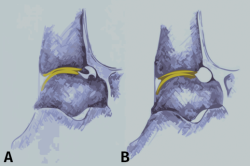

La planificación preoperatoria debe centrarse, como hemos señalado, en una correcta diferenciación entre el pinzamiento por lesión de tejidos óseos y blandos, ya que ello puede ser en ocasiones difícil de realizar bajo la visualización artroscópica. Además, como hemos manifestado también, los osteofitos podrían estar cubiertos por tejido cicatricial y/o sinovial inflamatorio, siendo difíciles de detectar y conduciendo, el no resecarlos adecuadamente, a peores resultados quirúrgicos(4,29,30). Es conocido que la identificación preoperatoria de los osteofitos se asocia con mejores resultados, siendo igualmente importante realizar una resección completa(15,19,31). La Figura 3 ofrece una visión general de la anatomía normal de la articulación del tobillo.

Figura 3. Visión lateral de un tobillo que muestra la zona de cartílago anterior de la tibia y la inserción de la cápsula. A: los osteofitos están a nivel distal de la tibia y en talus; B: anatomía tras resecar los osteofitos.